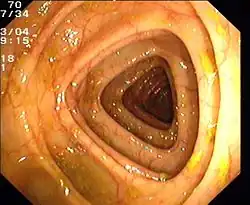

Normaler Dickdarm (Colon transversum)

Normaler Dickdarm (Colon transversum) -

Blick vom Colon ascendens in das Zökum, die Bauhinsche Klappe ist am rechten Bildrand zu sehen

Blick vom Colon ascendens in das Zökum, die Bauhinsche Klappe ist am rechten Bildrand zu sehen